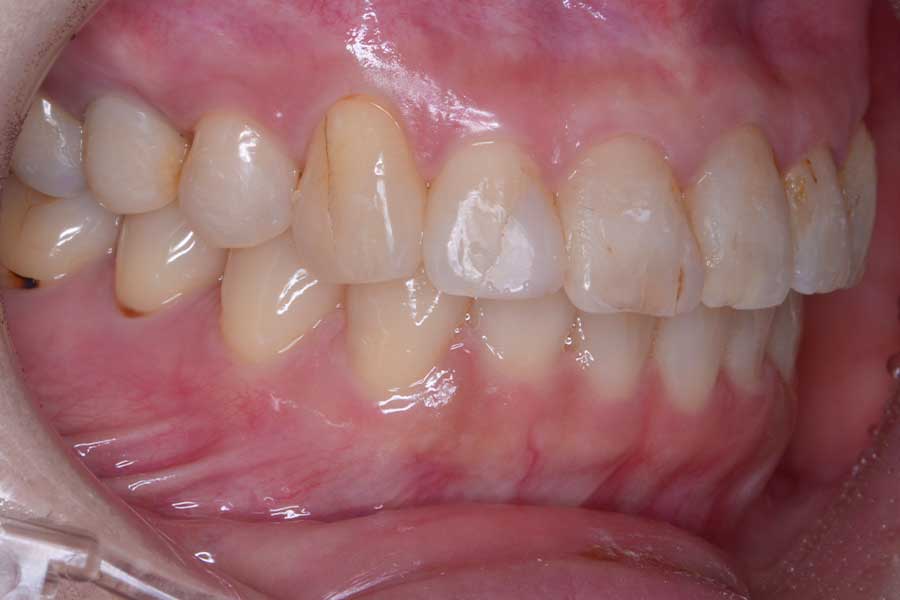

治療後

主訴 前歯の虫歯治療の前に飛び出た前歯を引っ込めたい

期間 7か月

治療内容 上顎ラビアル矯正(表側矯正)